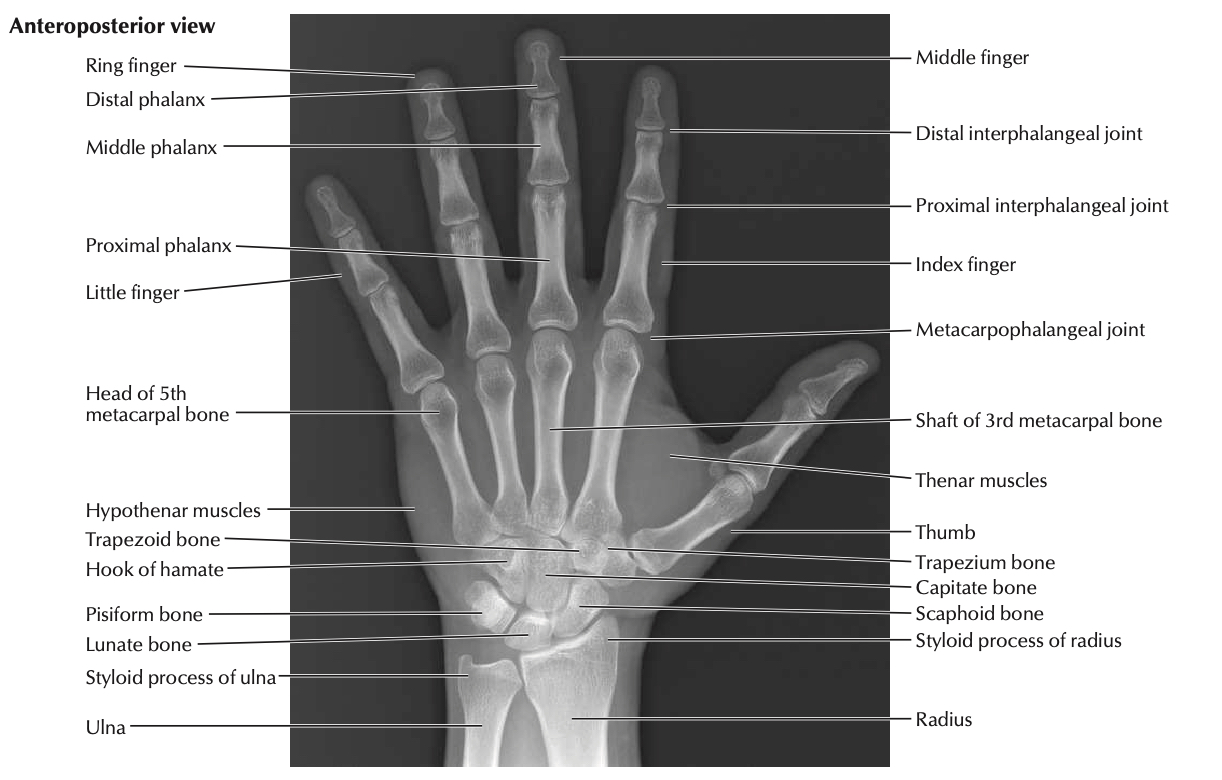

wrist radiograph interpretation

https://radiopaedia.org/articles/wrist-radiograph-an-approach

https://geekymedics.com/wrist-x-ray-interpretation-osce-guide/

https://www.aliem.com/emrad-wrist/